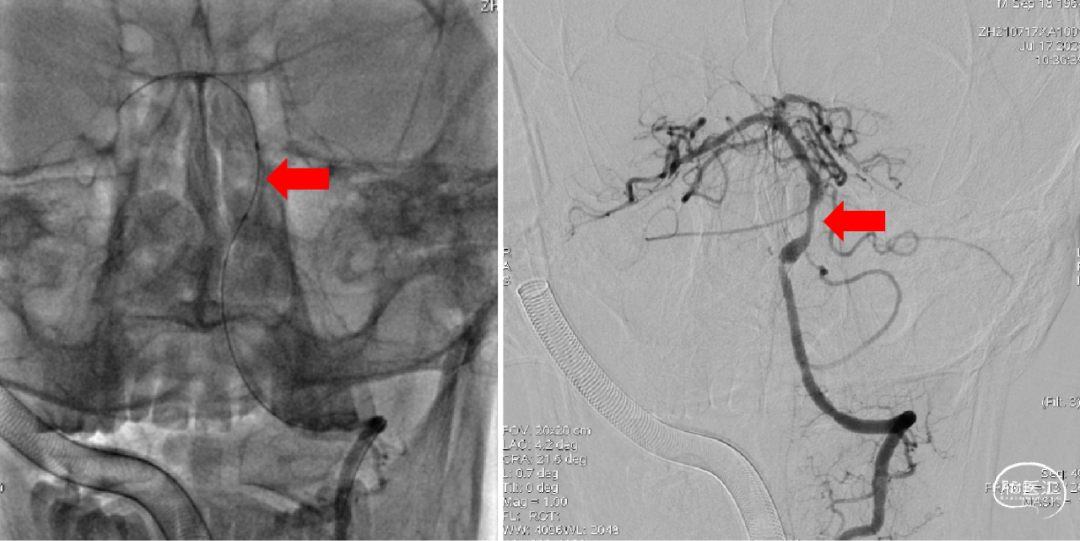

1、考虑右侧椎动脉V4段闭塞,不再犹豫,即刻选择左侧椎动脉入路;2、左侧椎动脉造影:提示V4段末端瘤样扩张伴基底动脉近端重度狭窄。

ACE60抽吸导管+RECO 4×20mm取栓支架抽拉结合,造影示基底动脉近端重度狭窄,远端通畅。

1、取栓两次,第二次将尼科支架置于狭窄处;2、第二次取栓后造影基底动脉近端重度狭窄,远端通畅。

1、术后即刻造影;2、15分钟后再次造影,基底动脉近端仍有重度狭窄,远端血流稀疏、缓慢。